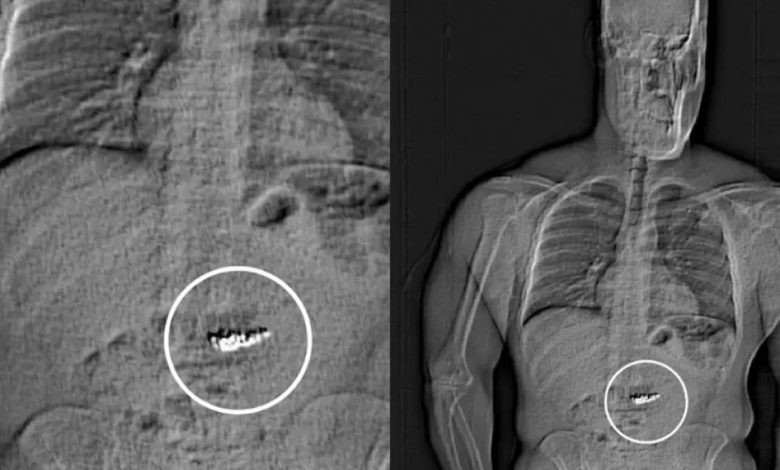

وبعد مطاردة قصيرة، قبضت الشرطة الأمريكية على الرجل بتهمة العصيان لأوامرها. وعند إخضاعه للفحص الطبي في مركز الاحتجاز، اكتشف المسؤولون وجود الأقراط داخل معدته.